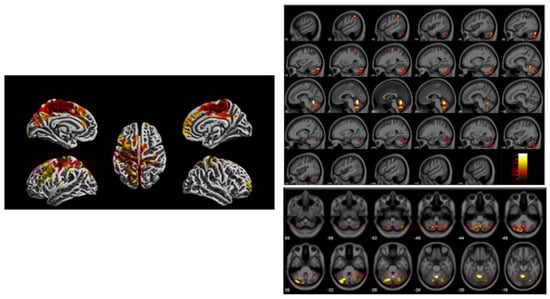

- Beckwith, T.; Cecil, K.; Altaye, M.; Severs, R.; Wolfe, C.; Percy, Z.; Maloney, T.; Yolton, K.; LeMasters, G.; Brunst, K.; et al. Reduced gray matter volume and cortical thickness associated with traffic-related air pollution in a longitudinally studied pediatric cohort. PLoS ONE 2020, 15, e0228092. [Google Scholar] [CrossRef] [PubMed]

| Early Childhood TRAP | MRI: SPM, VBM [6] | Adolescent | Reduced gray matter volumes, cortical thickness in sensorimotor regions, cerebellum | Beckwith et al. [34] |